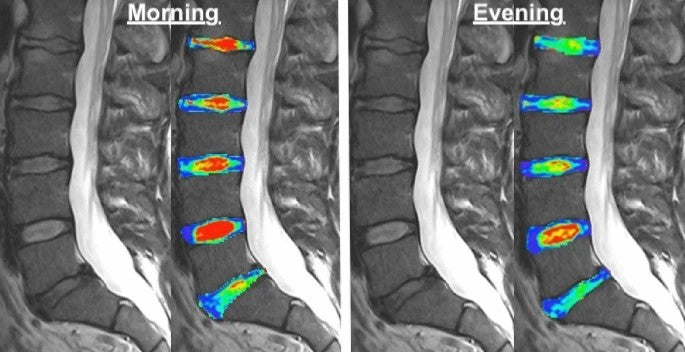

Zdrowy głęboki sen powinien stanowić 1/3 doby. Fizyczny odpoczynek po całym dniu jest jednak równie ważny. Krążki międzykręgowe wieczorem po całym dniu są obniżone w wyniku działania nacisku i utraty wody. Do rana krążki powinny odzyskać normalną wysokość a przy tym również nawodnienie. Jest to jednak ściśle powiązane z doborem materaca zarówno w zakresie twardości jak i składu materaca.